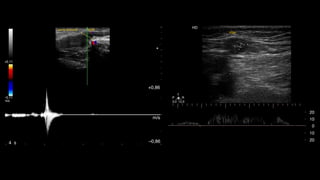

+0,86

m/s

–0,864 s

–0,11

+0,11

Vena femoral VSM

Figura 5 Imagen que demuestra el cierre valvular correcto

sin reflujo en la VSM con el Doppler color y espectral.

Figura 3 Doppler espectral con corte transversal evidencia

una VSM suficiente ante las maniobras de Valsalva.

Figura 6 Corte transversal de la VSM que muestra un aumento

base), ante las maniobras de Valsalva.

reverso ante lasmaniobras de Valsalva en la unión safena- femoral (viraje de color rojo, en descanso a color azul, en Valsalva). +0,86 m/s –0,864 s m/s –0,11 +0,11 Vena femoral VSM Figura 5 Imagen que demuestra el cierre valvular correcto sin reflujo en la VSM con el Doppler color y espectral. Figura 7 Insuficiencia de la VSM en el tercio medio del m ante las maniobras de Valsalva. - Para examinar el eje de la VSP, con el paciente de e das al operador, se realizan cortes transversales en la posterior de la pantorrilla (de caudal a cefálico), vis zando la vena safena parva y calculando el reflujo e distintos niveles. Debe consignarse si es o no tortuo a qué altura desemboca en la vena poplítea (si es lo hace)15 , midiendo la distancia desde la planta del A su vez, hay que evaluar la presencia o no de la safena parva del muslo y, en caso de que esté prese definir si esta es suficiente o insuficiente. - A nivel del hueco poplíteo se busca la existencia de re en la vena poplítea. - Si se descubre insuficiencia de la VSP, también debe indicar si el ostium está involucrado o si el reflujo se i más caudalmente, si hay presencia de venas epifasc dilatadas y los puntos de reentrada del flujo. - Es necesario explorar las venas tibiales posteriores, a riores y peroneas. ARTICLE IN PRESSRARD-60; No. of Pages 8 4 H. Berardi, A. Ciccioli VSM Izquierda + ,07 – ,07 m/s +55,90 –54,98 cm/s 2 1 0 Vena femoral VSM 5,3s Figura 3 Doppler espectral con corte transversal evidencia una VSM suficiente ante las maniobras de Valsalva. HD 20 10 0 10 20 T R 12,03,0 P VSM HD Figura 6 Corte transversal de la VSM que muestra un aumento de las velocidades anterógradas (por encima de la línea de base), ante las maniobras de Valsalva.